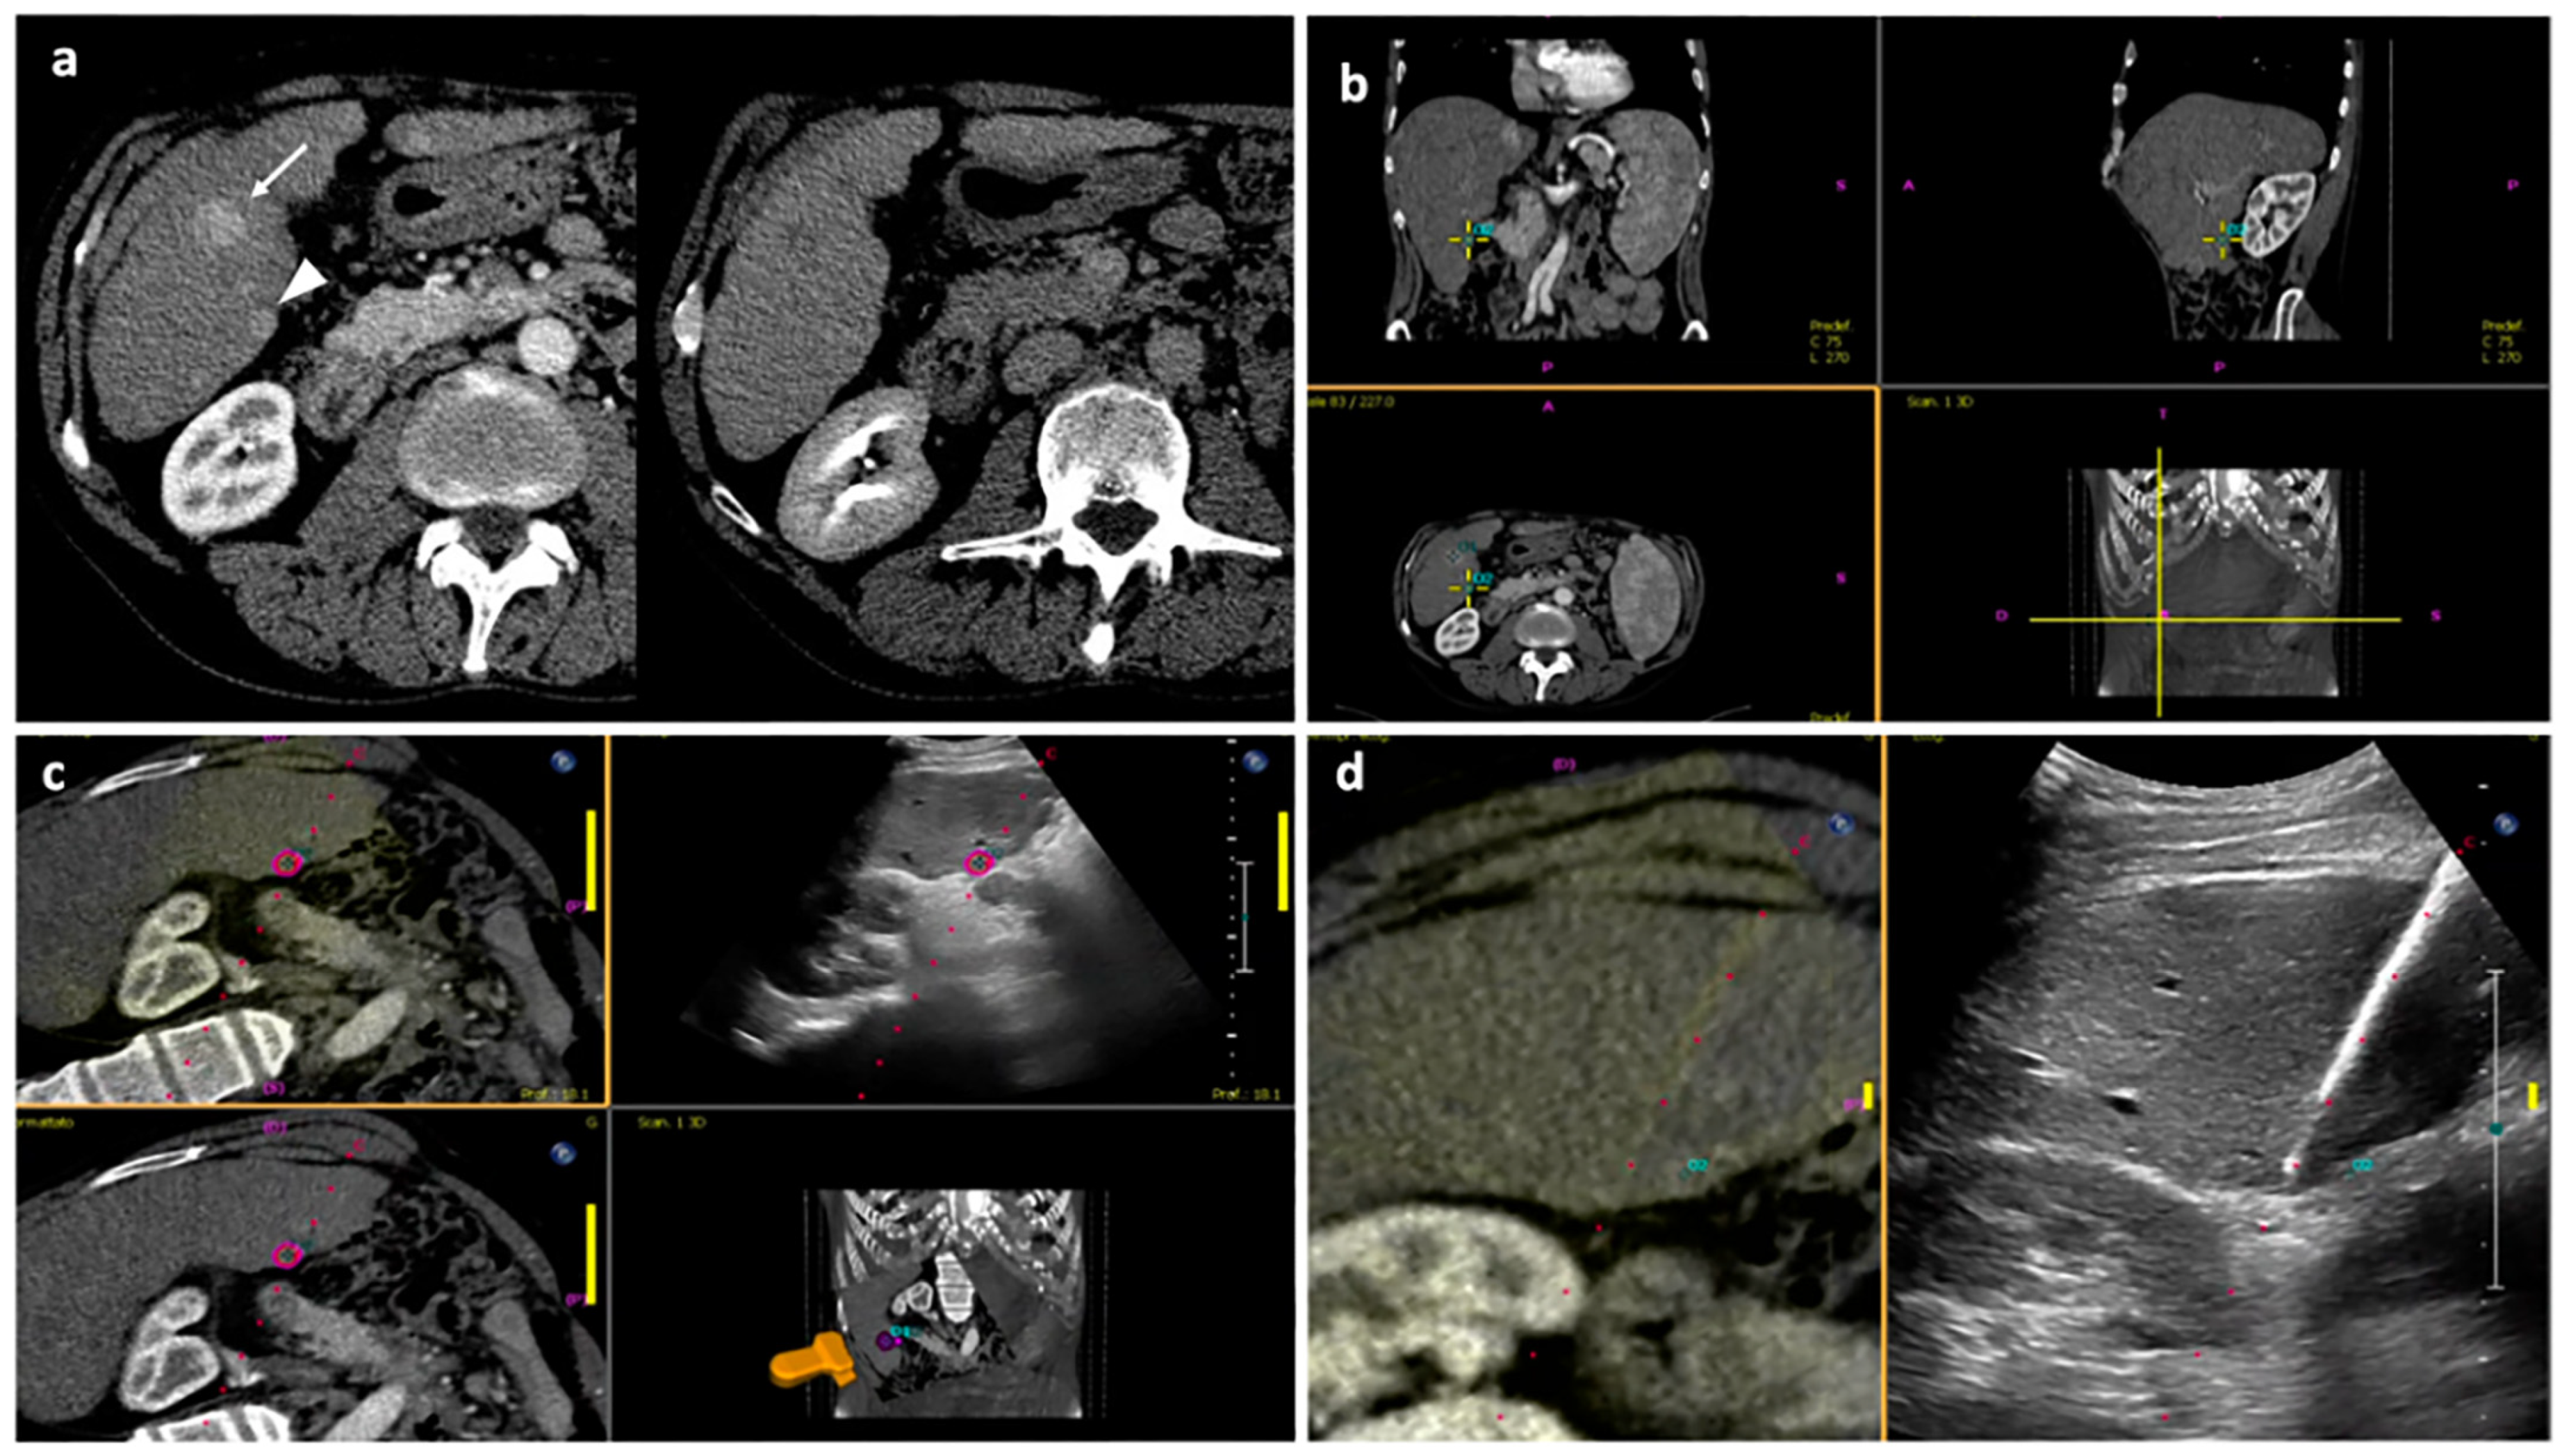

Since the precision of manual coregistration performed in CBCT fusion imaging can also be affected by anatomical distortion between the datasets and movement during CBCT acquisition, it is possible, but rare, at least in our experience, to obtain very different information from the two fusion imaging guidance techniques. Giving priority to the information provided by one over the other in this situation can be challenging. In the single patient in which no tumor control was observed at 1-month follow-up, the antenna seemed perfectly positioned with US fusion imaging, while it resulted completely out of the tumor following CBCT imaging information; since the registration quality appeared superior for US fusion imaging, the operator performed the ablation without moving the antenna, but CT images at 1 month almost perfectly resemble intraprocedural CBCT fusion images, with a complete miss (Figure 5). In this case, CBCT fusion imaging resulted to be superior, but the question of the imaging modality to give priority to when modalities provide different information remains open; generally, one should prefer the modalities that achieve the best registration, but this is hard to assess in a reasonable amount of time during procedure.

Figure 5. Missed target; (a) Axial CT image in the arterial phase showing a hypervascular nodule in S8, postero-lateral to an ablation volume from previous treatment, consistent with recurrent disease (white arrow). (b) US fusion imaging is performed by registrating pre-procedural CT images to real-time US images, and the antenna is placed within the target tumor. (c) CBCT fusion imaging indicates that the antenna and the predicted ablation volume (purple) are distant from the tumor (red contour), differently from what is suggested by US fusion imaging. Since the registration quality between US real-time images and pre-procedural CT images appeared good, the operator decided to ablate without repositioning the antenna. (d) CT axial image in the arterial phase at 1-month follow-up resulted comparable to intraprocedural CBCT fusion imaging, demonstrating that the nodule was missed.